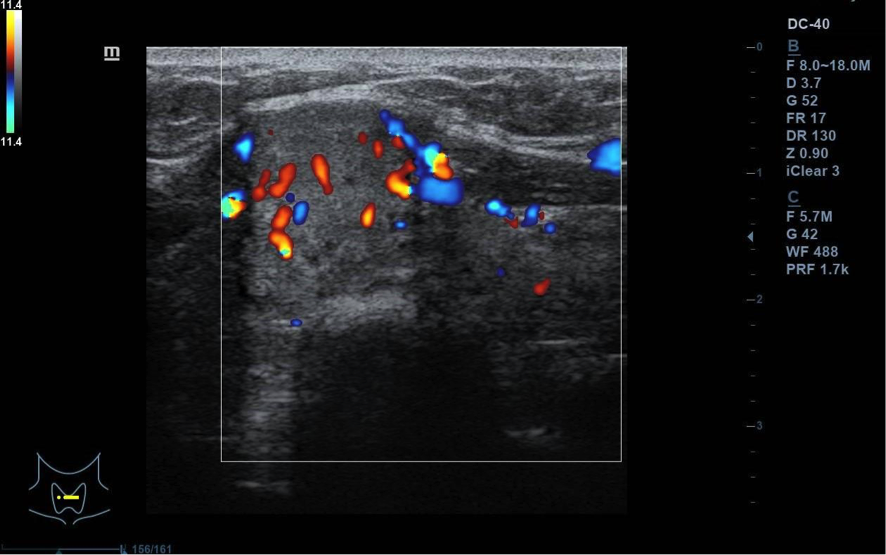

Se visualiza nódulo tiroideo en la unión del istmo con lóbulo tiroideo derecho, sólido, con cierta heterogenicidad, halo grueso anecogénico. Una zona del borde irregular, con mayor señal Doppler y de crecimiento excéntrico. Mide de diámetro máximo 25 x 20 mm. Adenopatías no patológicas.